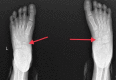

Kohler's disease is characterized by osteochondritis of the navicular bone due to various factors like the lack of blood supply and late ossification of the bone. In particular, it is a disease of the pediatric age group, which has male preponderance. It may present with bony pain unilaterally or, at times, be asymptomatic and diagnosed accidentally. Clinical presentation and radiological investigations are the mainstay of diagnosis. This self-limiting condition requires only symptomatic conservative management. A surgical approach is not yet indicated. One such case of bilateral Kohler's disease is presented in this report. Here, we discuss the disease's presentation, examination, treatment, and prognosis.